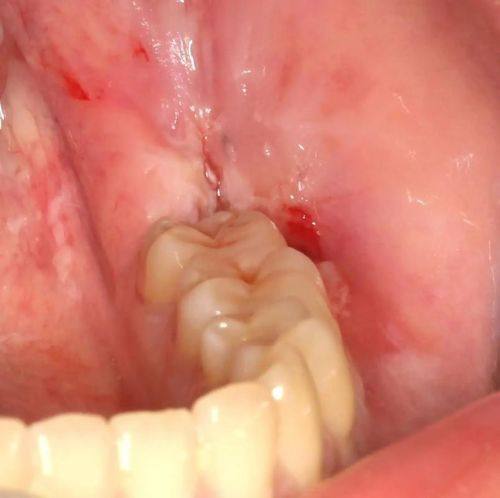

种植牙:由经验多的医生团队操作,搭配精良的数字化口腔诊疗设备,可精细评估患者的牙槽骨条件,制定适配的种植方案,保护种植牙后的稳定性、美观度与咀嚼功能,诊疗过程效率高安心。

补牙:针对不同程度的牙体缺损,采用适配的补牙材料,由经验多的医生操作,精细填充缺损部位,修复牙齿的形态与功能,补牙后成效自然,与原生牙色泽接近。

根管治疗:针对牙髓炎、根尖周炎等牙髓疾病,由专精医生操作,借助精良的诊疗设备精细清除感染牙髓,进行根管填充与修复,有效缓解牙齿疼痛,保留患牙。